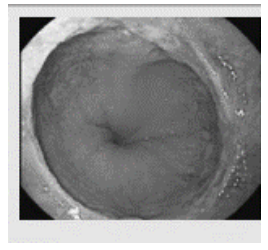

Analise a imagem endoscópica abaixo para responder à questão.

Considerando a imagem acima, o achado demonstrado corresponde